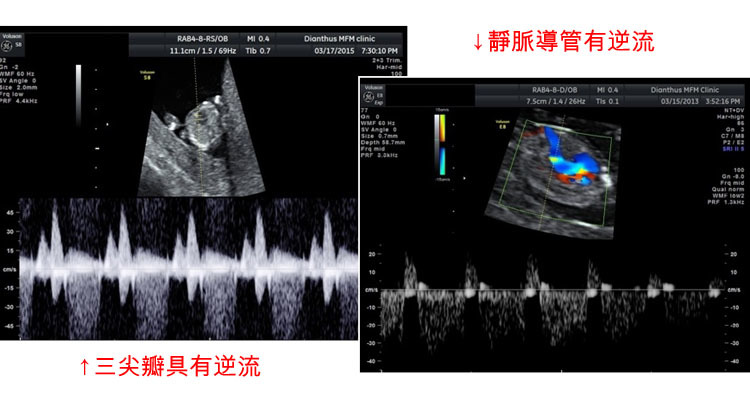

高層次超音波與染色體異常 Dr Chen 透視胎兒的世界 痞客邦